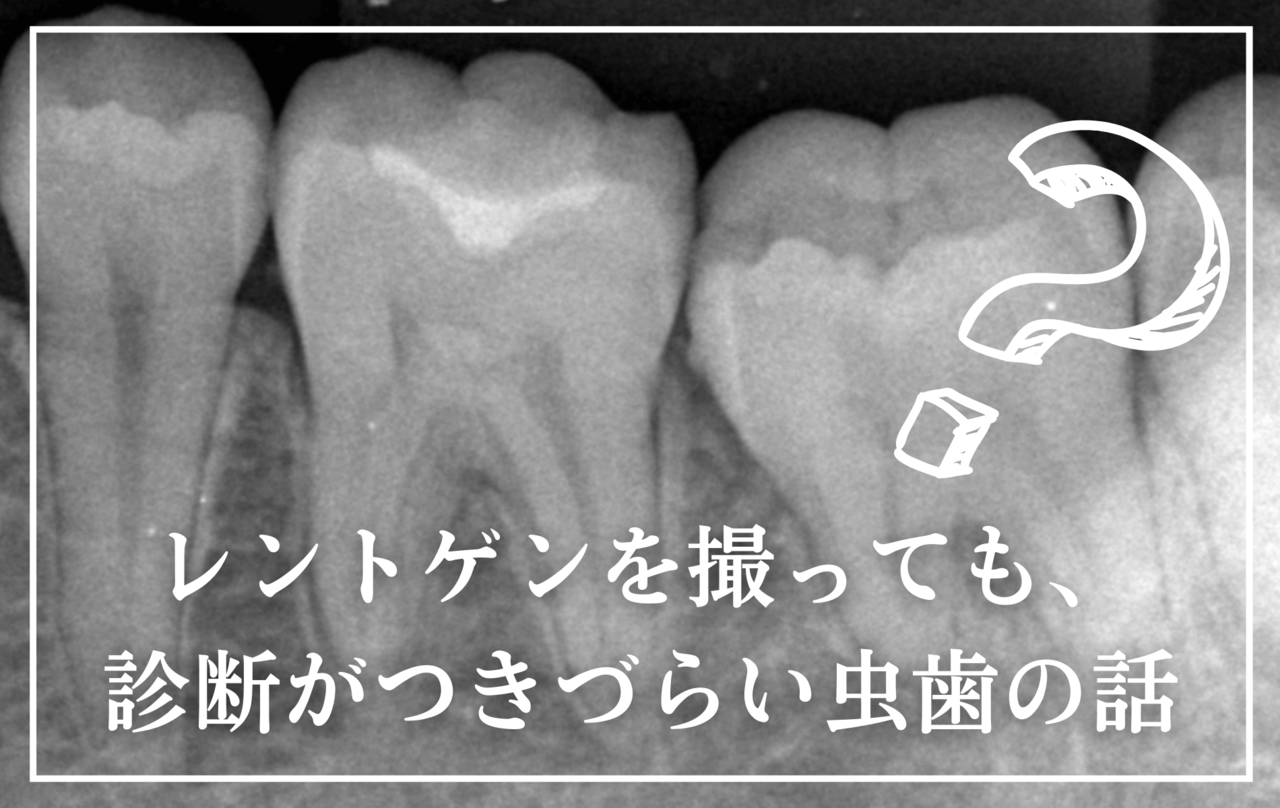

この虫歯の怖いところは「特に発見しにくいこと」にあります。

歯と歯の間ですから自身では見つけにくく、歯科医師でも肉眼では発見できないことが多いです。

レントゲン写真で見つかる事も多いですが、それでもうまく隠れてしまい100%発見できるとは限りません。

定期メンテナンスに通われている方は、外観からの微妙な違和感や、歯石除去時のひっかかりなどから、比較的早い段階で見つかる事が多いです。